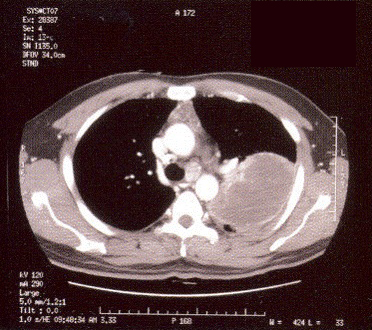

The patient was a 36-year-old man with a smoking history of 15 pack-years. He was a non- drinker and worked as a van driver delivering chicken. He enjoyed good past health and gave no recent traveling history. He first became unwell in Jan 2001 when he noted increasing lethargy, headache, jaw numbness and dry cough. He saw various GPs without improvement and was eventually admitted into a HA hospital on 13/1/2001 with worsening jaw pain and a cough which was now productive of bloodstained sputum. He had a low-grade fever on admission. His admission CXR showed a huge left upper lobe mass and right upper lobe nodules (Fig 1). A CT thorax confirmed a necrotic lung mass with mediastinal lymphadenopathies (Fig 2). Bronchoscopy was performed via the oral route due to nasal congestion and there was complete occlusion of his left upper lobe orifice with nodular mucosa in the right upper and middle lobes. The endoscopic diagnosis was carcinoma of the lung but both the histology of the bronchoscopic biopsy and a subsequent fine needle aspiration of the lung lesion yielded necrotic material only. He was treated with antibiotics and analgesics for presumed chest infection but his condition deteriorated with increasing respiratory distress.